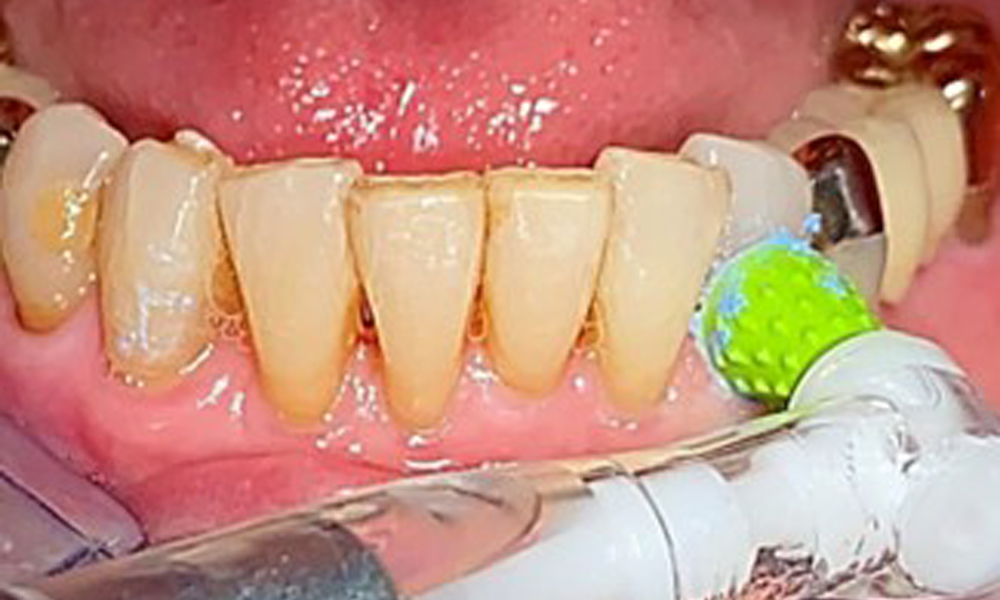

The patient was fitted with a combined removable maxillary telescopic prosthesis more than 25 years ago (Fig. 1, Fig. 2, Fig. 3) and is very happy with her dentures. The patient has an adequate fixed denture for the mandible (Fig. 4).

The patient brushes her teeth and implants three times a day with a manual toothbrush and single-tuft brush. She also uses interdental brushes once a day in the evening. She also cleans her prosthesis after every meal.

The dental findings are as follows: Combined removable implant and tooth-supported telescopic prostheses on implants 15, 13, 21, 23, 24, 25 and tooth 11 (Fig. 1, Fig. 2, Fig. 3). The patient was fitted with a fixed mandibular denture. Adequate bridges were present over 37 to 34 and 45 to 47 (Fig. 4), the crown margins were intact and there were no active caries. A composite filling with a marginal gap was present on tooth 43. There was mandibular gingival recession, exposing 1 to 3 mm of root surface. This also applies to 11.

A single-tufted brush is specifically recommended for the telescopic prostheses (Fig. 8) and the patient should be advised on the appropriate interdental brush size (Fig. 9). The patient has been implementing these recommendations for intraoral hygiene at home for many years and was encouraged to continue during the professional preventive dental appointment.